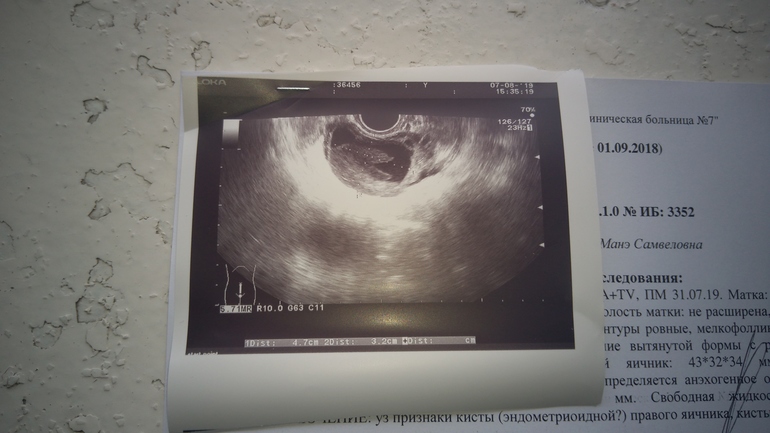

Со 100% точностью дать характеристику кисты можно только наблюдая,за ней несколько циклов. Если киста не меняет свои размеры или на обор становится больше, то это однозначно эндометриойдная. Если она уменьшается или исчезла, то это киста фолликула

Вообще киста небольшая. Овуляция вряд ли будет, но лапароскопия сразу - странно. Сходите к гинекологу нормальному.